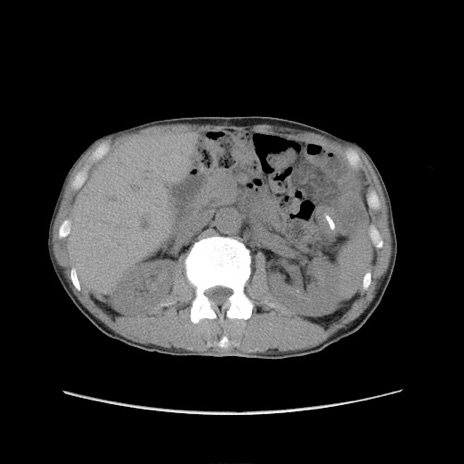

症例11(横断像)

【症例】 60歳代男性

【主訴】 下腹部痛

【現病歴】 本日夜中より下腹部痛の症状認め、受診。

【既往歴】 膀胱癌(膀胱全摘+尿管皮膚瘻術) 、胃癌術後

【身体所見】 BT 35.3℃、PR 58/min、BP 136/98mHg、腹部平坦、軟、腸蠕動音±、ストマ留置あり、左上腹部~正中部に圧痛あり、反跳痛なし。

【データ】WBC 5100、CRP0.01